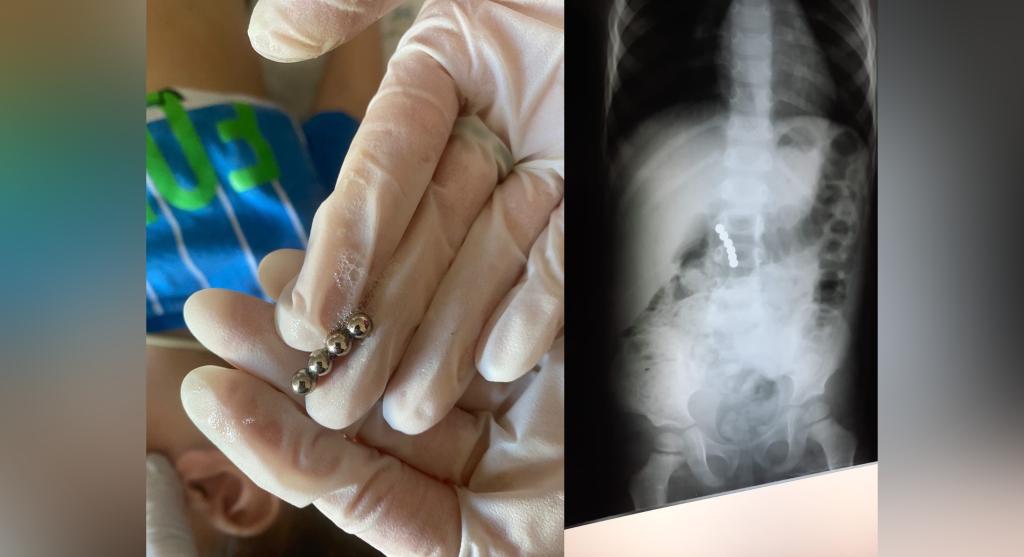

В Башкирии хирурги извлекли из желудка 4-летнего ребенка 6 игрушек-магнитов. Об этом рассказал глава Минздрава республики Айрат Рахматуллин.

Попадание подобных шариков в кишечник крайне опасно тем, что магниты соединяются друг с другом через петли кишечника, что может привести к перфорации и перитониту.

С помощью эндоскопа врачи вытащили шарики. Ребенок уже пошел на поправку и сегодня будет выписан из больницы.